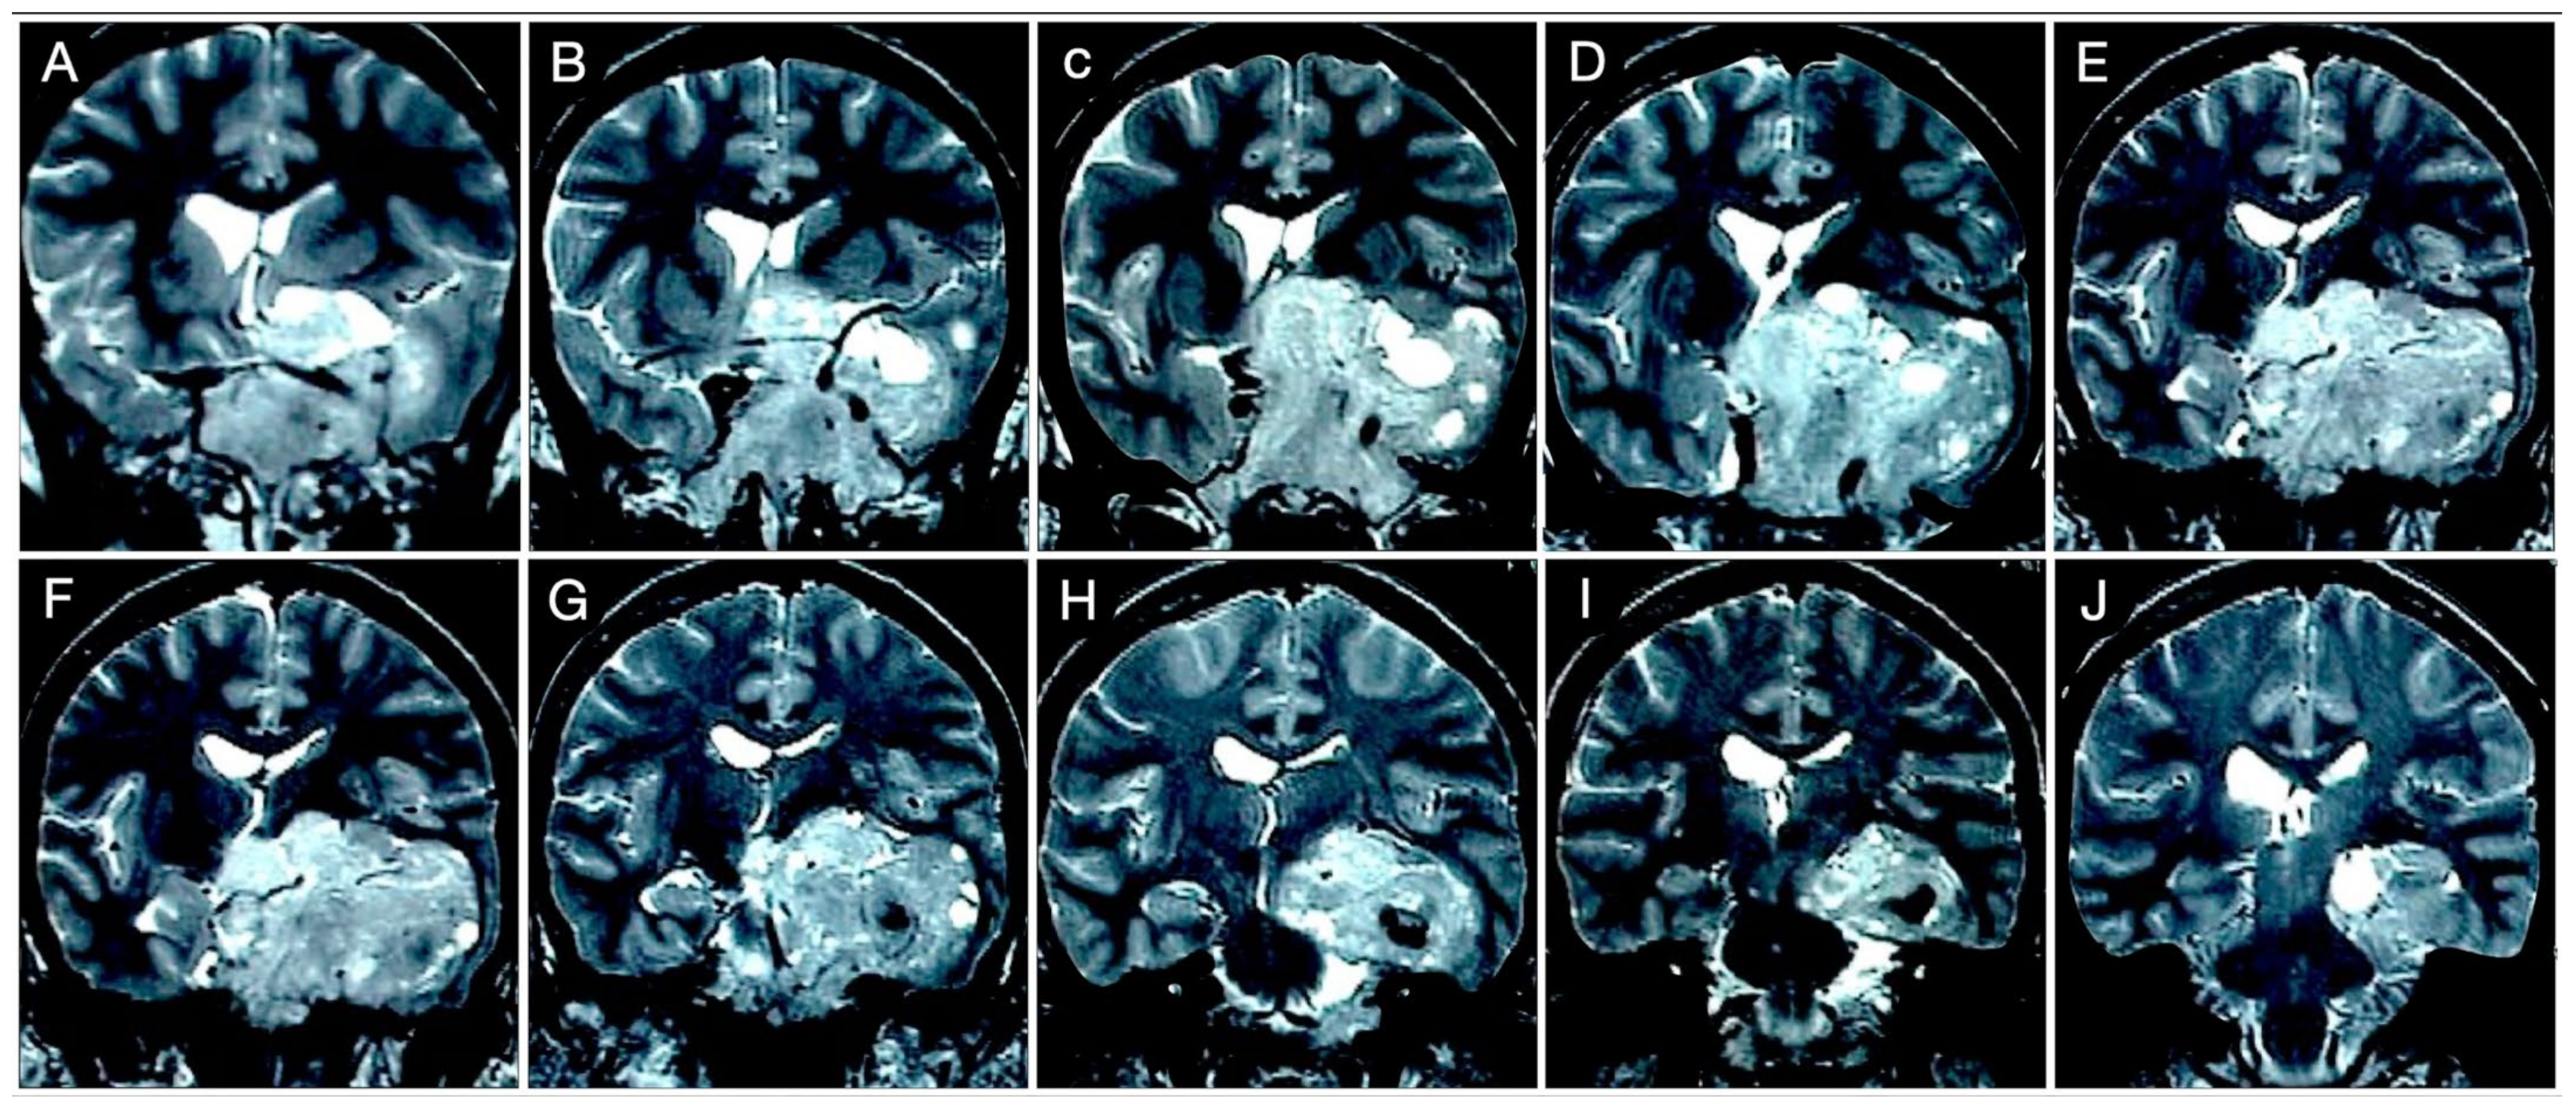

3.2.2. Case #3: Paramedian Pattern of Growth with Parenchymal Invasion

3.3. Parasellar Extension

3.3.1. Case #4: Involvement of the Middle Skull Base with Parenchymal Invasion

3.6. Brain Parenchymal Invasion

Case #8: Aggressive ACTH Tumor with Multiple Recurrences